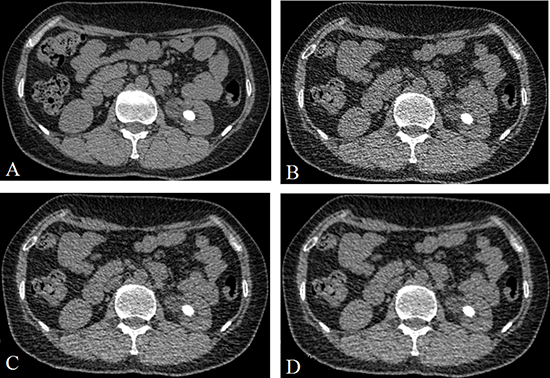

Figure 1: A 48 years old man with a stone (14.2 mm × 10.3 mm × 13.1 mm) in the left kindy. (A) CDCT images, reconstructed with FBP; (B) LDCT image, reconstructed with FBP; (C) LDCT image, reconstructed with 60% ASIR; (D) LDCT images, reconstructed with 80% ASIR. The stone size were no obvious difference between the A and D.